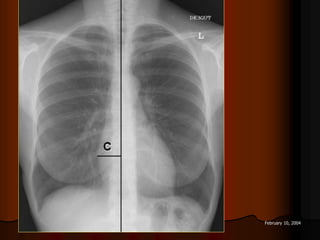

KYÕ THUAÄT

PHIM NGÖÏC THAÚNG SAU-TRÖÔÙC

7 February 10, 2004

Phim ngöïc thaúng chuaån(standard chest XR):

Theá sau-tröôùc:Tia X ñi töø sau löng ra

tröôùc ngöïc ñeå tim khoâng bò phoùng ñaïi.

Khoaûng caùch töø ñaàu ñeøn ñeán

cassette: 1,8m(6 feet).

Beänh nhaân ñöùng ngay ngaén,ngöïc aùp

saùt cassette,hai tay choáng naïnh vaø

ñöa hai khuyûu tay ra tröôùc ñeå taùch hai

xöông baû vai ra khoûi loàng ngöïc.